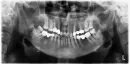

Здравствуйте! У меня было неудачное протезирование в 1913 году. Долго искала хорошего врача. Он удалил часть зубов и предложил поставить импланты: внизу справа два (6-й и 7-ой) и в верху слева два(7-й и 8-й). После установки коронки верхних имплантов проходят как бы над языком. Врач сказал, что это моя особенность, но через некоторое время (подтачивая зубы по высоте то с одной стороны, то с другой несколько раз) согласился, что не хватает теперь 8-ки в низу слева. Мне очень неудобно, так как язык западает и натирается, и высота прикуса уменьшилась, языку стало мало места и он травмируется по бокам о зубы и натирается сверху и сбоку с двух сторон. Импланты были установлены 20 ноября, последнюю коррекцию врач сделал за 1,5 недели до Нового года и теперь устаю даже говорить. Первоначально я договаривалась, что мосты в верху надо менять, но он сказал, что стоят и пусть стоят. Под левым мостом в верху у меня стали частые воспаления в виде гнойничков и боли. Мост врач снял 28 января, но сломал зуб (это 6-ка, но на этом месте была 5-ка), на уровне десны и штифт сломался. Врач сказал, что или сделает металлическую вкладку или удалит корень и поставит импланты. Что лучше? Устоит ли мост на вкладке? Можно ли увеличить высоту прикуса и как? Врач сказал, что теперь увеличить высоту прикуса нельзя, так как другие зубы не будут контактировать. До этих многократных коррекций высоты зубов языку хватало места, он не натирался и не зажимался... Врач челюстно-лицевой хирург всё делает сам, репутация хорошая, но мне что-то не очень везёт... Заранее огромное Вам спасибо! С уважением к Вам Ольга.

Прикрепленые фото

Добрый день, уважаемая Ольга. Лично я не понимаю, для чего нужно было устанавливать имплантаты на место восьмого зуба. На мой взгляд, это полная неграмотность. Также, протезирование на имплантатах, на мой взгляд, некорректное и нерациональное.

Да и лечение каналов и коронки оставляют желать лучшего.

Что касается подтачивания и коррекции коронок по прикусу в полости рта, это говорит о крайней непрофессиональности. Рекомендую, не продолжать никаких действий, так как, судя по увиденному, ничего хорошего вам не светит. Приезжайте к нам, я вас посмотрю, и все вам расскажу, в письме сложно разъяснить вам рациональный план лечения.